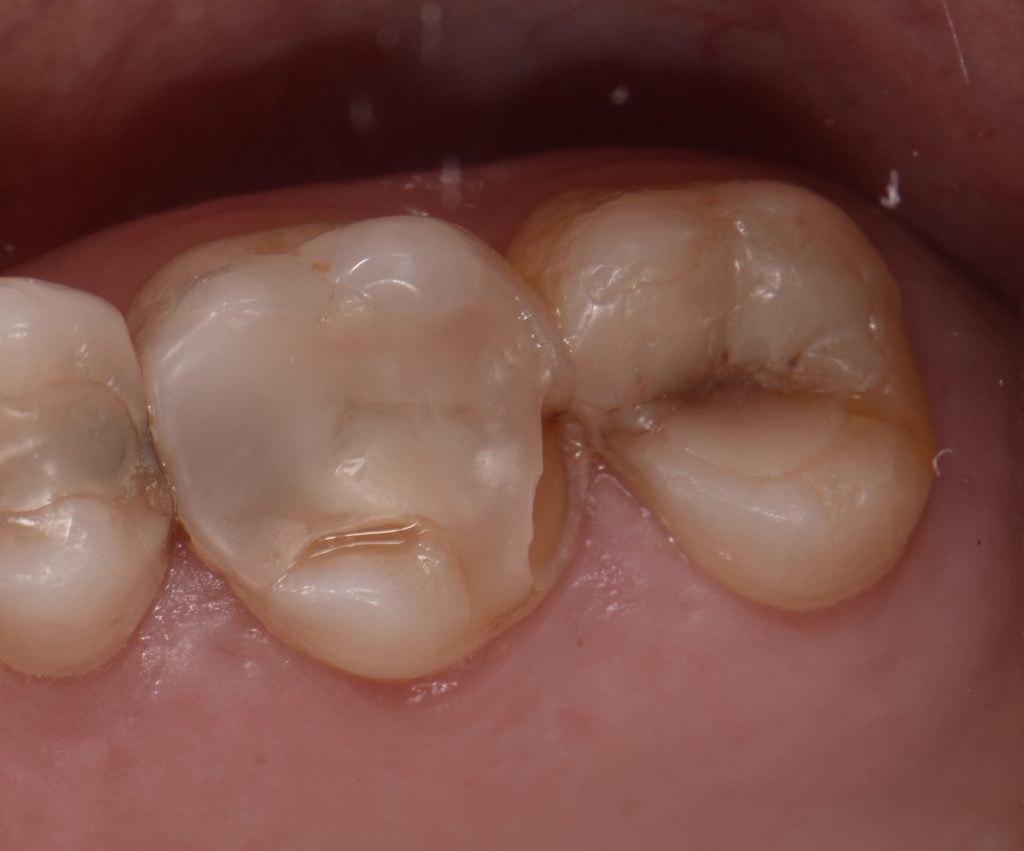

The same is found with a fracture of a cusp or fragment of a tooth that has an intra-coronal restoration, such as an inlay, an amalgam, or a composite resin. (Figs. 5-6)